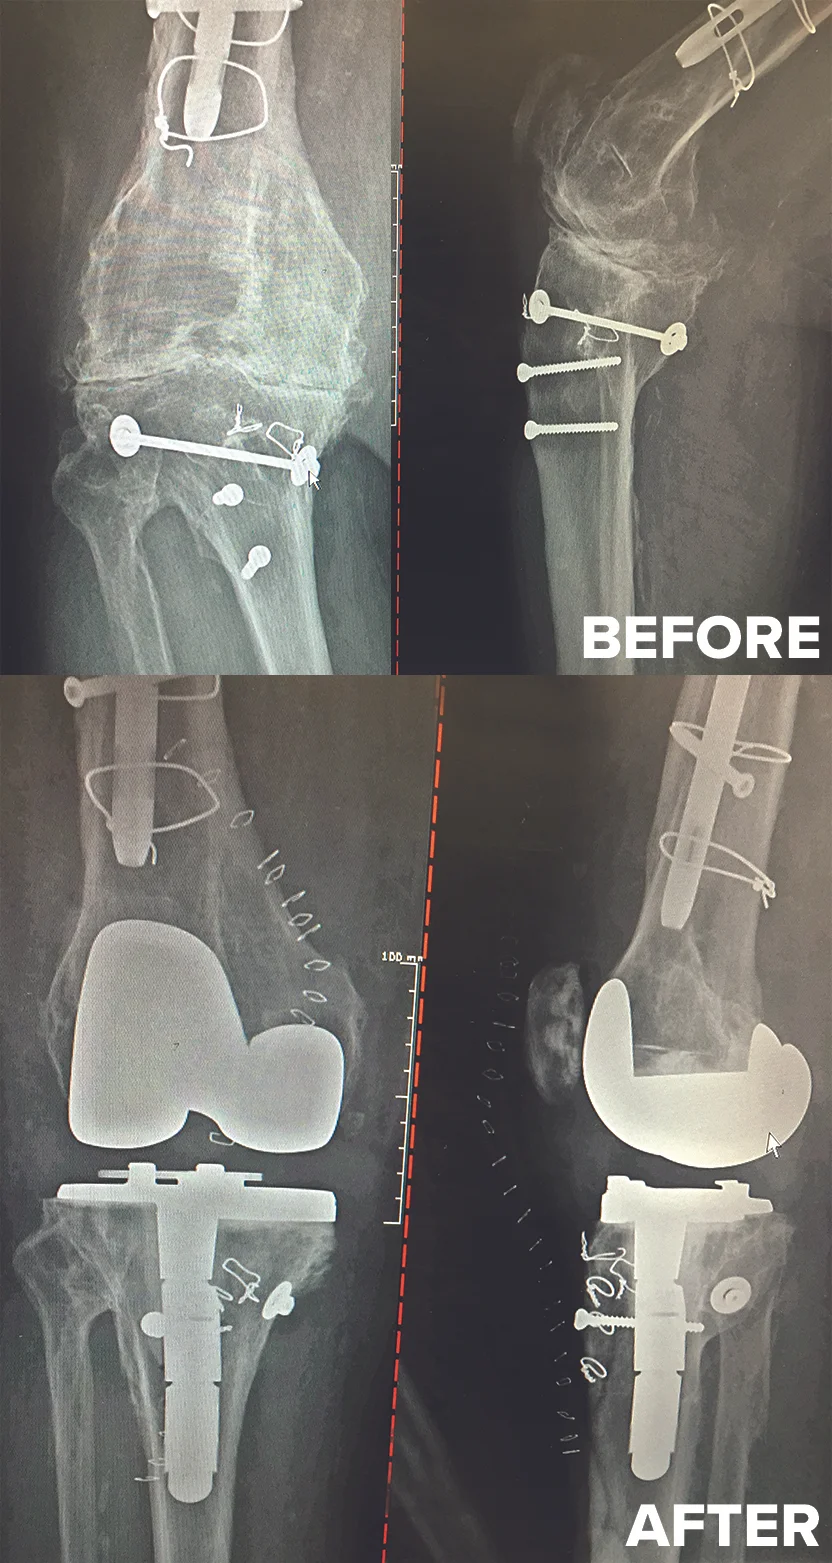

Before: Bone on bone

After: Total Knee Replacement

OMNI

Before: Post traumatic knee arthritis with retained screws, rod, wires and deformity

After: Complex Total Knee Replacement - leg now straight

BIOMET REVISION

Before: Previous Ligament surgery

After: Total Knee Replacement on 45 y/o female